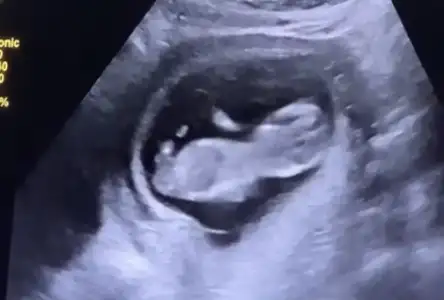

Merhaba arkadaşlar. Bugün koyu renkli kanamadan dolayı acile gittim. Bebek 10+6 olmuş. Kalp atışları da iyiydi. Rahimde bir şey görünmüyor. Ama ilk defa böyle koyu kırmızı kan gördüm. Benim durumda olan var mı? Dualarınızı bekliyorum...

Eklentiler

• IMG_20230512_155722.webp

IMG_20230512_155722.webp

23 KB · Görüntüleme: 60

Benim ilk defa oldu hocam, ultrasonda da birşey görünmedi. Kalp atışı da iyi dedi. Korkulacak birşey yok dedi ama içimiz hiç rahat değil :(

Benim ilk defa oldu hocam, ultrasonda da birşey görünmedi. Kalp atışı da iyi dedi. Korkulacak birşey yok dedi ama içimiz hiç rahat değil :KK43:

Ultrasonda kanama alanı görünmemesi ilginç .bana kanaman pıhtılı ve parça vs olursa sıkıntı demişti doktor. sonrasında 1.5 ay progestan kullandım ağızdan ve vajinal fitil şeklinde .kahverengi lekelenme şeklinde devam etti ve tamamen geçti.